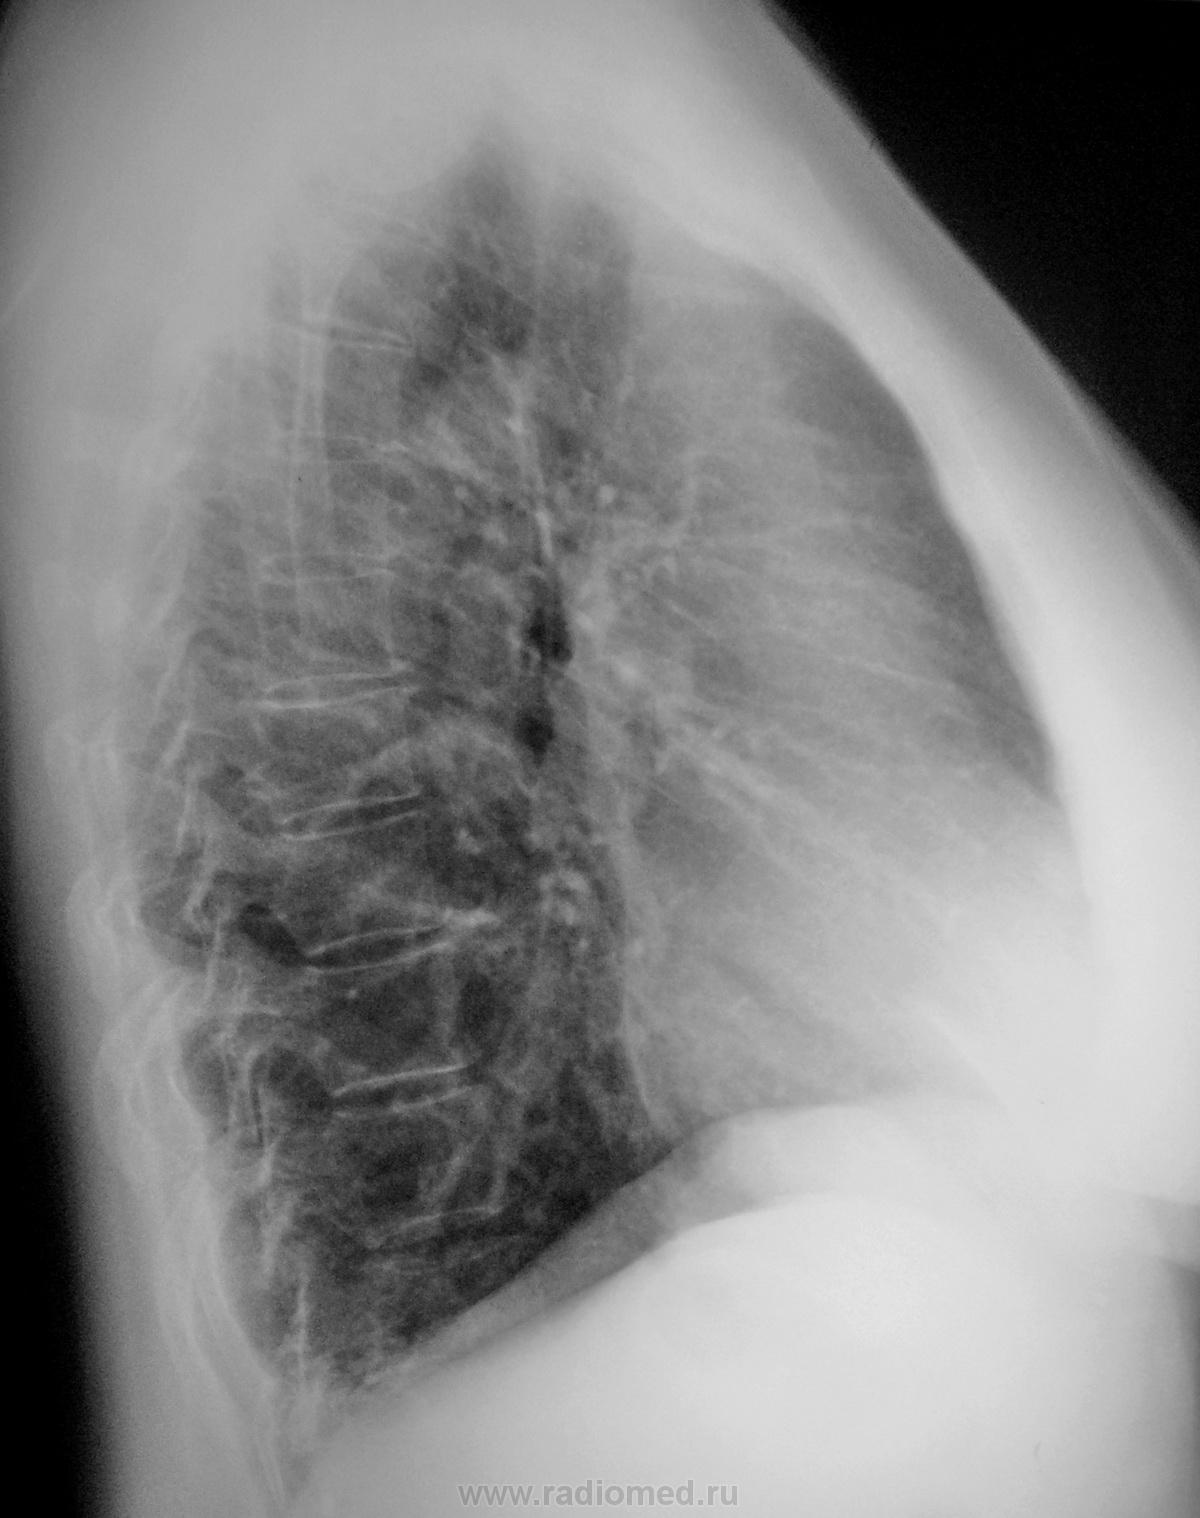

Пол пациента: Женский пол Тип патологии: Инфекция Область исследования: Грудная клетка и верхние дыхательные пути Методы исследования: Rg Женщина 50 лет обратилась с жалобами к терапевту по поводу высокой температуры(39) и кашля, была направлена на снимок. Я поставил пневмонию в S5 правого лёгкого, но немного засомневался. Что скажут уважаемые коллеги? https://radiomed.ru/sites/default/files/styles/case_slider_image/public/user/712/sl274012.jpg?itok=m1MWVr3r ID:17022 Чт, 24/11/2011 - 20:43 #1 DR.RAD Не на сайте Был на сайте: 11 лет 9 месяцев назад Зарегистрирован: 25.03.2009 - 18:22 Публикации: 805 да инфильтрация сомнительна Чт, 24/11/2011 - 22:43 #2 Bob Не на сайте Был на сайте: 11 лет 11 месяцев назад Зарегистрирован: 20.08.2011 - 20:06 Публикации: 218 есть только в S7 Чт, 24/11/2011 - 21:44 #3 Nikolas Не на сайте Был на сайте: 2 месяцев 1 неделя назад Зарегистрирован: 21.12.2010 - 20:37 Публикации: 4559 с носоглоткой у пациентки, точно, не все в порядке. Чт, 24/11/2011 - 22:36 #4 И.Бондаренко Не на сайте Был на сайте: 2 дня 5 часов назад Зарегистрирован: 13.09.2011 - 22:55 Публикации: 9206 Посмотрим, что покажет лечение. Возможно, вы и правы. Чт, 24/11/2011 - 22:45 #5 stovbav Не на сайте Был на сайте: 2 года 2 месяцев назад Зарегистрирован: 20.12.2009 - 17:28 Публикации: 7066 Все таки есть небольшое локальное утолщение передне-базального отдела косой м\долевой плевры справа, да и рядом смазаность легочного рисунка, так что истина недалеко. А вот контроль не помешает. Болезни ног: виды, симптомы, причины, профилактика и лечение Пт, 25/11/2011 - 02:09 #6 Makcimalist Не на сайте Был на сайте: 11 лет 9 месяцев назад Зарегистрирован: 08.05.2010 - 14:28 Публикации: 1994 stovbav wrote: Все таки есть небольшое локальное утолщение передне-базального отдела косой м\долевой плевры справа, да и рядом смазаность легочного рисунка, так что истина недалеко. А вот контроль не помешает. - При таком застое в МКК отмеченные Вами изменения бывают. Инфильтрации в паренхиме не усматриваю... пока! -------------- "Просто, по видимости, не видеть логики в очевидных вещах - это тоже одно из свойств некоторых умов, наряду с грустными думами о свойствах ума других." © Vega 08/10/2011

Все таки есть небольшое локальное утолщение передне-базального отдела косой

м\долевой плевры справа, да и рядом смазаность легочного рисунка, так что истина недалеко. А вот контроль не помешает.

- При таком застое в МКК отмеченные Вами изменения бывают.

Инфильтрации в паренхиме не усматриваю... пока!